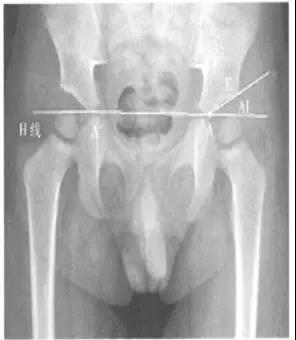

- CE角(Wiberg 的中心边缘角):即两侧股骨头中心连线的垂线和髋臼外缘股骨头中心连线所成的夹角。

- 正常值:20°~35°

- 临床意义:主要用于评估髋臼的包容性,髋臼发育不良时夹角变小。

- Sharp角:即双侧泪滴下端连线与泪滴下端至髋臼上缘连线所成的角。

- 正常值:33°~38°

- 临床意义:<32°很少见且无临床意义39°~42°为正常值的上限,42°~47°需动态观察,>47°可认为异常。评价髋臼发育和髋臼对股骨头的覆盖情况。

- 髋臼指数(actebular index,AI,亦称髋臼角):髂骨最下缘与髋臼最外缘的连线与H线的夹角(H线,即Hilgenreiner线,组成两侧髋臼髂骨最下缘的连线),适合于“Y”型软骨尚未闭合的儿童(≤10岁)髋臼的测量。

- 正常值:国外一些学者也测量了1~2岁婴幼儿的正常值范围,认为1岁婴儿的正常值在25°~30°之间,2岁一般低于20°,而超过30°为异常。

- 临床意义:评价髋臼发育和髋臼对股骨头的覆盖情况。